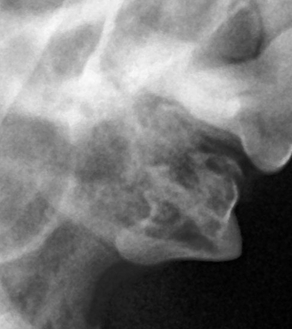

치아흡수성병변(FORL)은 치아가 안쪽에서부터 녹아 내리는 질환입니다. 치아의 뿌리(치근)나 치아의 머리(치관)의 정상적인 조직이 서서히 파괴되면서 염증성 조직으로 자리잡게 됩니다. 심한 경우에는 치아가 부서지거나, 피가 나고, 얼굴이나 치아를 만지는 것을 싫어합니다. 또한 통증으로 특히 건사료를 먹을 때 많이 불편해 하는 질환입니다. 특히 이 질환은 초기엔 겉으로 잘 보이지 않고, 잇몸 위로는 멀쩡해 보여도 치아 내부에서 이미 진행되고 있는 경우가 많습니다. 눈에 띄기 어렵지만 통증은 크고, 치료가 늦어질수록 심한 치통과 스트레스, 삶의 질 저하로 이어질 수 있습니다.

덴탈 X-ray를 통해 치아 내부 상태를 정확히 파악한 후, 아이에게 불필요한 고통 없이 최선의 결정을 내릴 수 있도록 안내합니다.